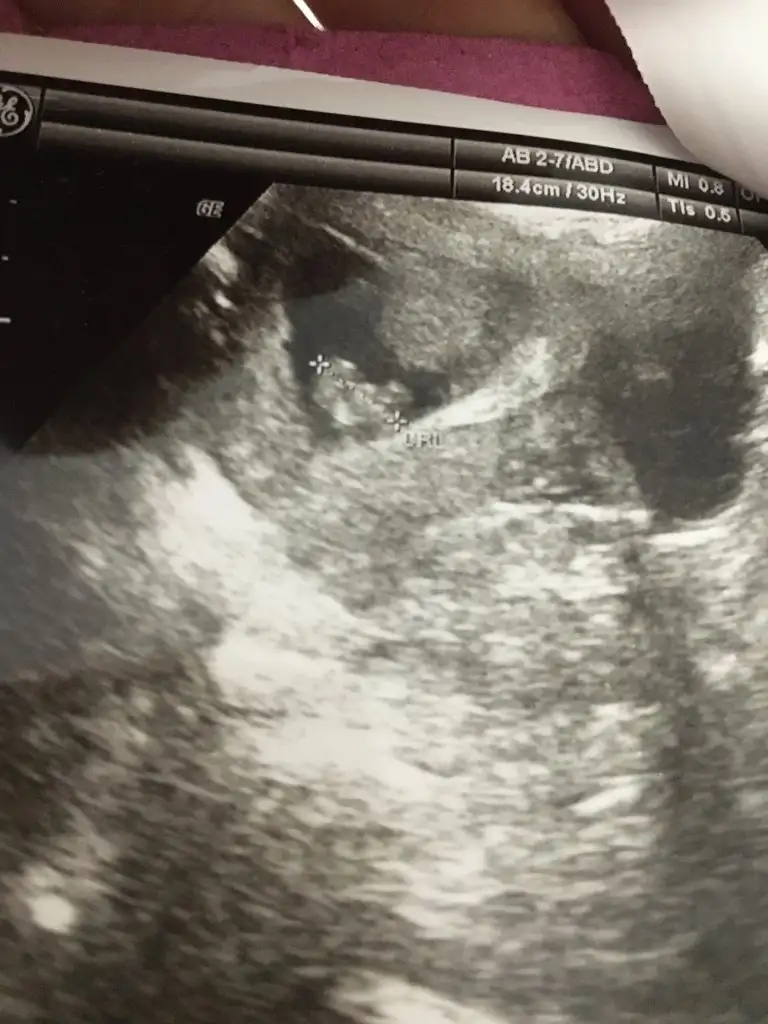

Banada bakarmısınız kız mı erkek mi 🙏

Yorumlarmisiniz rica etsem kizmi erkekmi